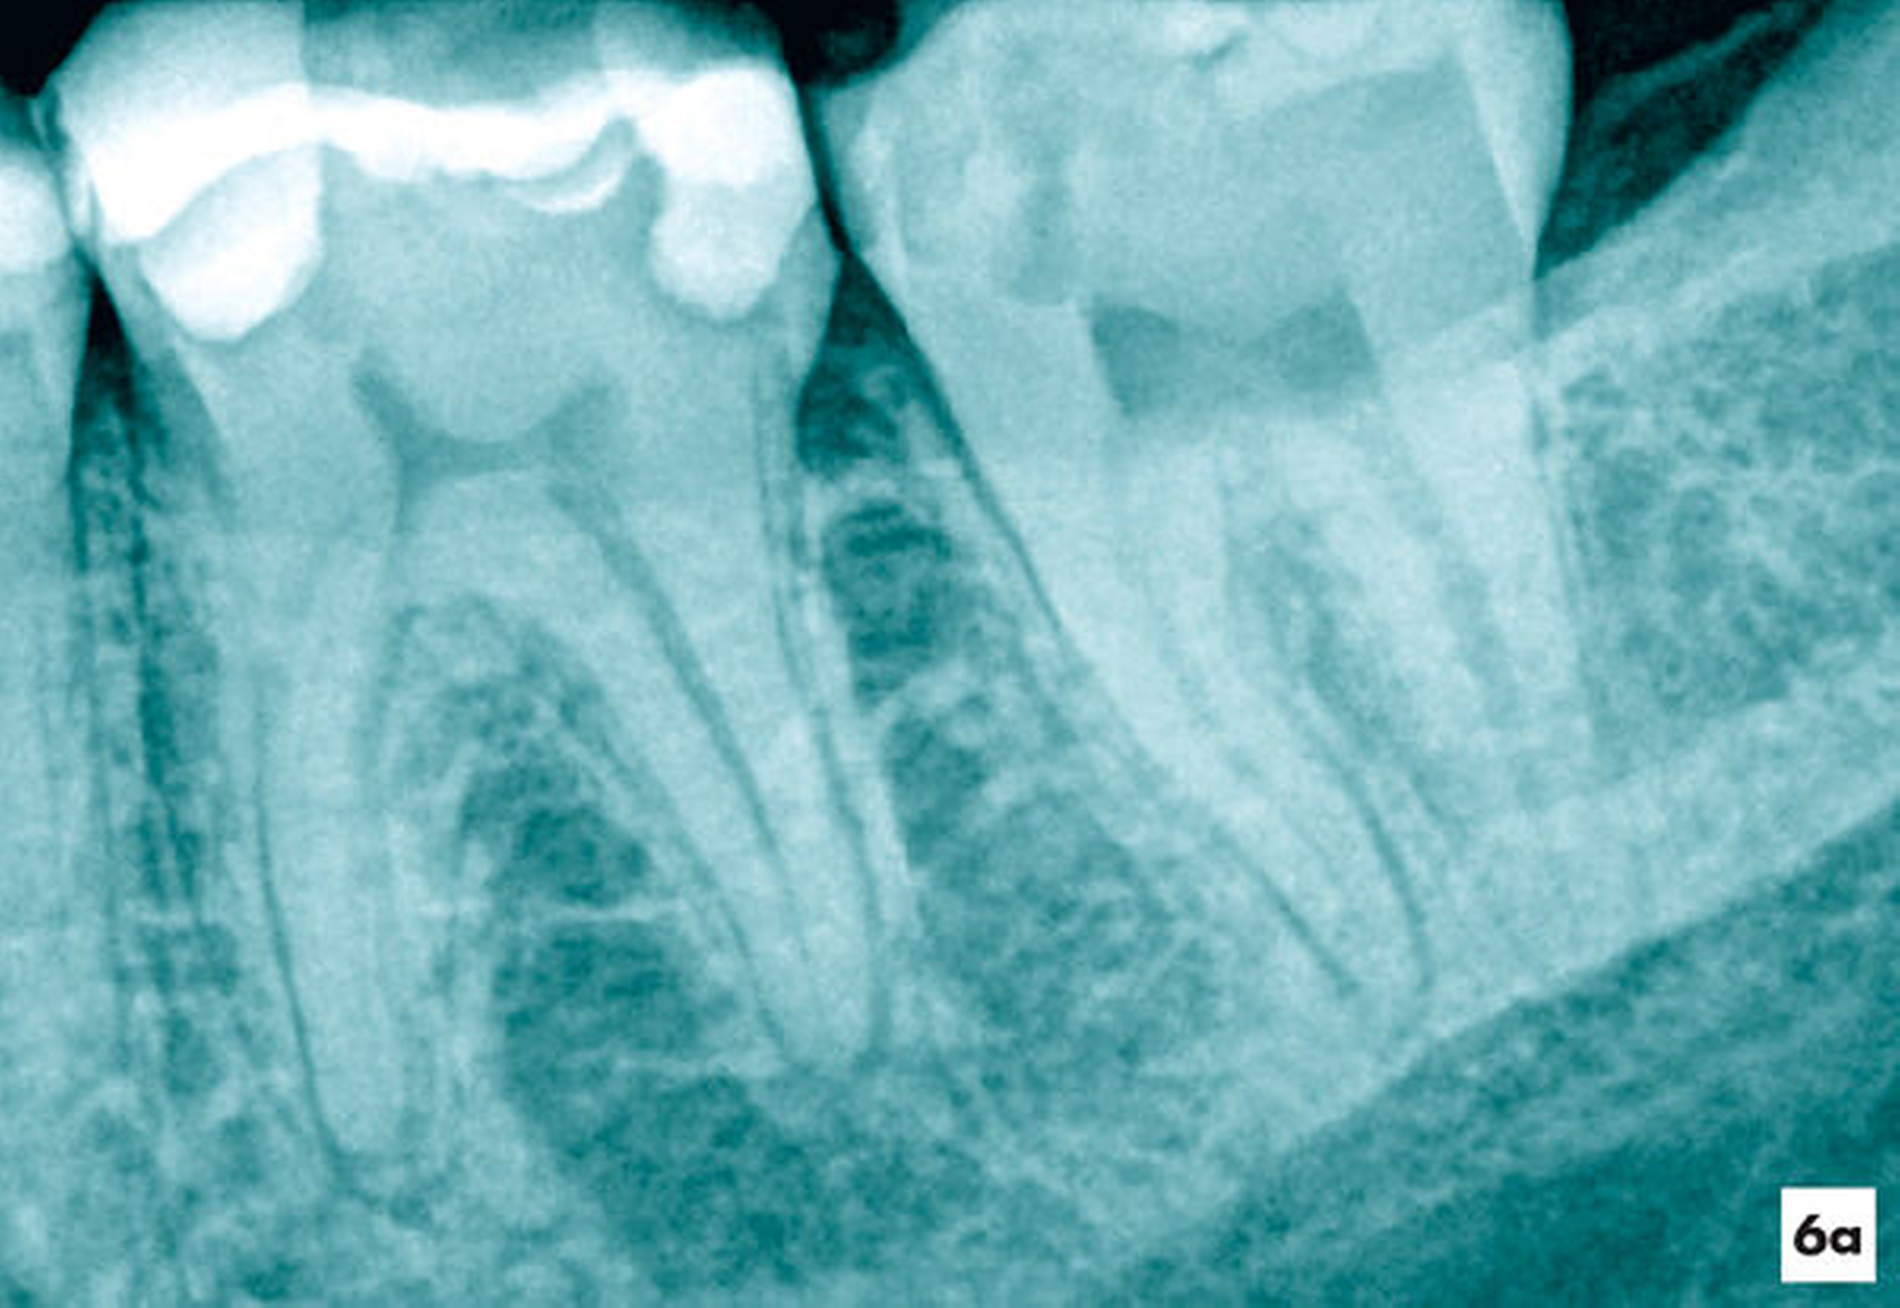

Eine 22-jährige Patientin verspürte nach einer direkten Überkappung mit Ledermix am Zahn 37 pulsierende Schmerzen. Die wiederholte Einnahme von Ibuprofen 400 führte nicht zu Schmerzfreiheit. Der Zahn wies keine pathologischen Sondierungswerte auf, war jedoch mit Zahnbeweglichkeit Grad II im Vergleich zum Restzahngebiss gelockert und perkussionssensibel. Es bestand der Verdacht auf eine irreversible Pulpitis (Abbildung 6a).

Unter Kofferdam wurde das Verschlussmaterial entfernt. Im Bereich der offen liegenden Pulpakammer ließ sich bei achtfacher Vergrößerung ein Pustropfen erkennen (Abbildung 6b). Daraufhin wurden das Pulpakammerdach im Bereich der ehemaligen kariösen Läsion und das Pulpagewebe oberflächlich unter Wasserkühlung mit einem Diamant abgetragen (Abbildung 6c). Nach einer zehn Minuten andauernden Oberflächendesinfektion mit 3-prozentigem NaOCl und Spülung mit Kochsalzlösung kam es zu keiner weiteren Blutung. Das intakte und homogen durchblutete Pulpagewebe ließ vermuten, dass die Pulpa weiterhin erhalten bleiben kann, so dass die etwa 5 mm2 große Pulpawunde mit MTA abgedeckt wurde. Die Kavität wurde mit Komposit verschlossen. Die Schmerzsymptomatik klang bereits nach einem Tag vollständig ab.

Zum Einjahresrecall reagierte der Zahn auf den thermischen und elektrischen Sensibilitätstest positiv. Die Zahnbeweglichkeit war physiologisch und röntgenologisch erschien der Desmodontalspalt im Vergleich zum Ausgangsbild in normaler Breite (Abbildung 6d).